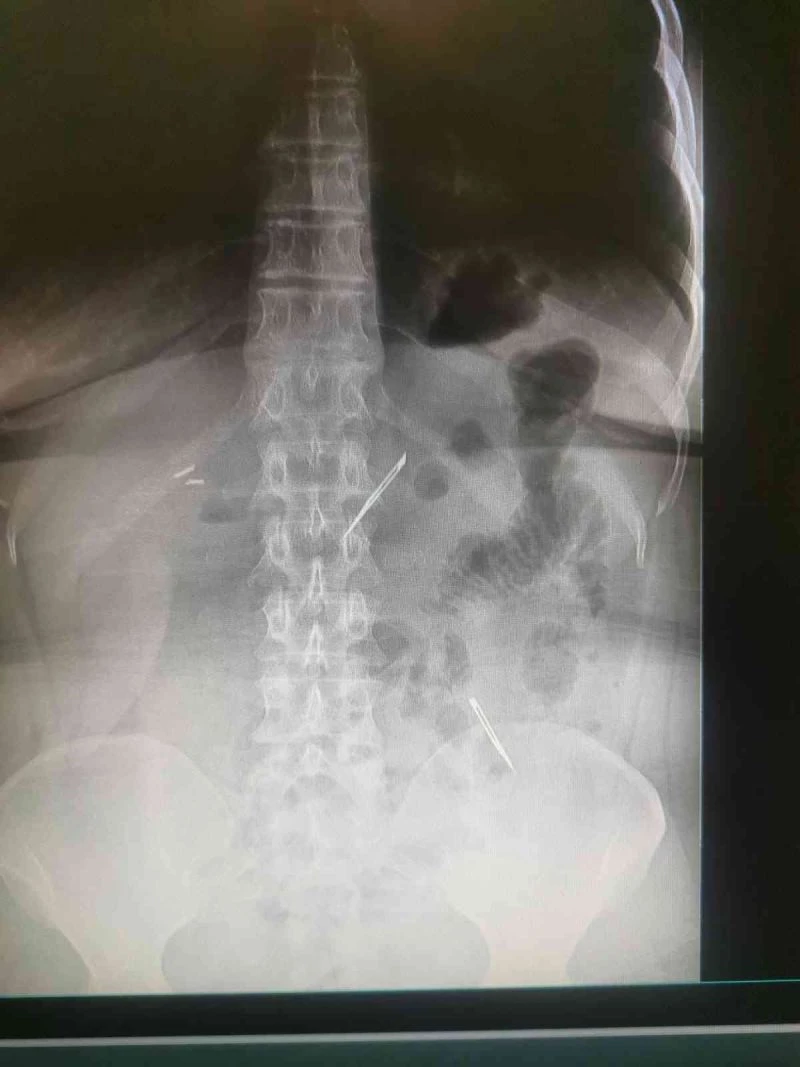

Sağlık Bilimleri Üniversitesi Ankara Atatürk Sanatoryum Eğitim ve Araştırma Hastanesi’ne mide ve karın bölgesinde aşırı ağrı şikayeti ile müracaat eden 46 yaşındaki D.E.’nin yapılan tahlil, tetkik ve çeşitli görüntülemelerden sonra bağırsak kısmında 2 adet neşter olduğu tespit edildi. Genel cerrahi kliniği tarafından zorlu bir ameliyat sonrasında neşterler kadının vücudundan çıkarıldı. 46 yaşındaki D.E. neşterleri nasıl yuttuğunu bilmediğini tahminen ekmek ile birlikte yutabilmiş olabileceğini ifade etti. Ameliyatı gerçekleştiren Sağlık Bilimleri Üniversitesi Ankara Atatürk Sanatoryum Eğitim ve Araştırma Hastanesi Genel Cerrahi Kliniği Eğitim ve İdari sorumlusu Prof. Dr. Hakan Buluş ise hastanın yoğun şikayetleri üzerine çektikleri röntgen sonrasında 2 adet neşteri görünce şaşkına uğradıklarını söyledi.

Hastanın şikayetlerinin artması üzerine gerçekleştirilen tetkiklerde 46 yaşındaki kadının karın bölgesinde 2 adet yabancı cisim olduğunu tespit ettiklerini, detaylı inceleme sonucunda bu cisimlerin neşter olduğunu fark ettiklerini belirten Prof. Dr. Buluş, “Yaklaşık 10 gün önce kliniğimize karın ağrısı ve bulantı şikayetleri ile başvurdu. Bizim yaptığımız fiziki muayene ve tetkiklerinde hastanın direkt karın grafisinde 2 adet yabancı cisim olduğunu tespit ettik. Aslında yabancı cisim bizim güncel grafiğimizde sık karşılaştığımız bir durum değil, fakat nadir de olsa görebildiğimiz bir patoloji. Biz de bunun üzerine ayrıntılı değerlendirmeler ve tetkikler yaptık. Sonrasında 2 adet yabancı cismin bistüri (neşter) ile uyumlu olduğunu gördük. Bunun üzerine hastanın şikayetlerinin de artması üzerine, ameliyat kararı verdik. Yaptığımız ameliyatta ince bağırsağın yaklaşık 180’inci santimetresinde bu yabancı cisimlerin olduğunu tespit ettik. Bunun üzerine ameliyatla bunları çıkarttık. Hastamızın sağlık durumu şuan gayet iyi. Ameliyattan sonraki üçüncü günü. Şuan bir problemi yok, inşallah birkaç gün içerisinde şifa ile taburcu etmeyi düşünüyoruz” şeklinde konuştu.

Çıkardıkları cismin, neşterin normalde ameliyatlarda kullanılan bir malzeme olduğunu söyleyen Prof. Dr. Buluş, “Çıkardığımız yabancı cisimler bizim ameliyatlarda sıkça kullandığımız 11 numara dediğimiz bir bistüri tipi. Ebatları da yaklaşık 4 santime yarım santim ebatlarında. Ucunun sivri olması nedeniyle ince bağırsak mukozasına saplanarak enflamasyon ve bir karın ağrısı yapması, sonrasında da ağrı şikayetlerinin artmasına neden olmasından dolayı ameliyat kararı verdik” diye konuştu.